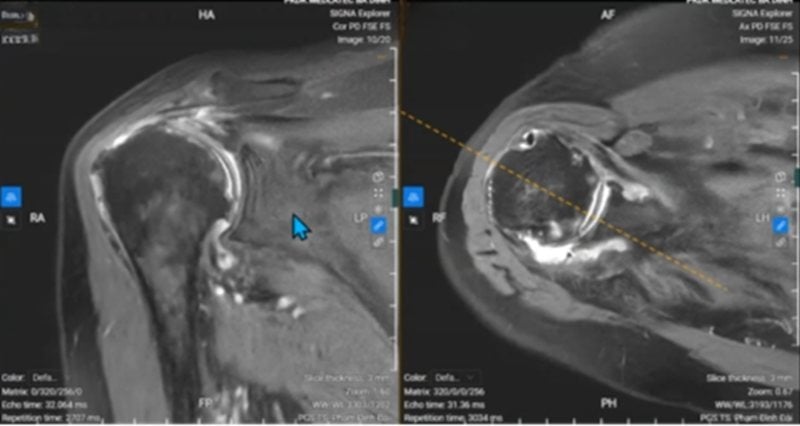

В ходе клинического обследования у г-жи Х. был первоначально диагностирован плечевой периартрит, характеризующийся скованностью, затруднением большинства движений и многочисленными болезненными точками вокруг сустава при надавливании. Для точной оценки степени поражения врач назначил магнитно-резонансную томографию (МРТ).

Результаты показали, что плечевой сустав пациента имел множество серьезных повреждений: тяжелую дегенерацию, полную потерю хрящевой системы головки плечевой кости, околосуставные спайки, отслоение хряща суставной впадины, скопление жидкости в плечевом суставе и дегенерацию плечевого сустава.

К наиболее распространенным методам относятся рентгенография, ультразвуковое исследование и магнитно-резонансная томография (МРТ). МРТ является наиболее ценным методом, позволяющим комплексно оценить повреждение мягких тканей вокруг сустава и внутренних структур плечевого сустава.